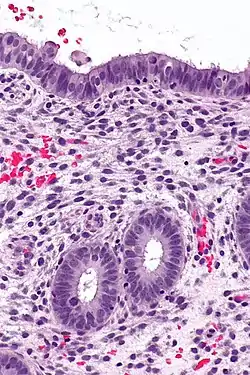

![]() Endometrium in the proliferative phase | |

Structure

The endometrium consists of a single layer of columnar epithelium plus the stroma on which it rests. The stroma is a layer of connective tissue that varies in thickness according to hormonal influences. In the uterus, simple tubular glands reach from the endometrial surface through to the base of the stroma, which also carries a rich blood supply provided by the spiral arteries. In women of reproductive age, two layers of endometrium can be distinguished. These two layers occur only in the endometrium lining the cavity of the uterus, and not in the lining of the fallopian tubes.[4][5]

- The functional layer is adjacent to the uterine cavity. This layer is built up after the end of menstruation during the first part of the previous menstrual cycle. Proliferation is induced by estrogen (follicular phase of menstrual cycle), and later changes in this layer are engendered by progesterone from the corpus luteum (luteal phase). It is adapted to provide an optimum environment for the implantation and growth of the embryo. This layer is completely shed during menstruation.

- The basal layer, adjacent to the myometrium and below the functional layer, is not shed at any time during the menstrual cycle. It contains stem cells that regenerate the functional layer,[1] which develops on top of it.